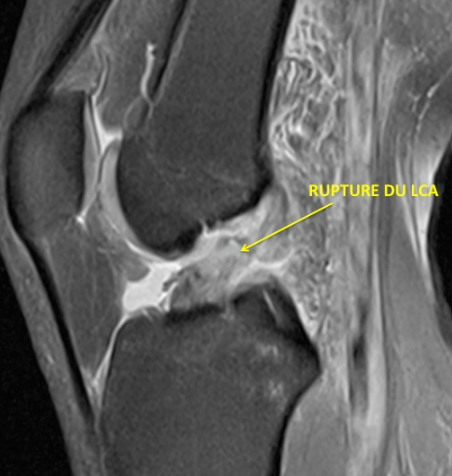

IRM

Une radiographie et un IRM permettront de faire le diagnostic

Centre orthopédie Aubagne